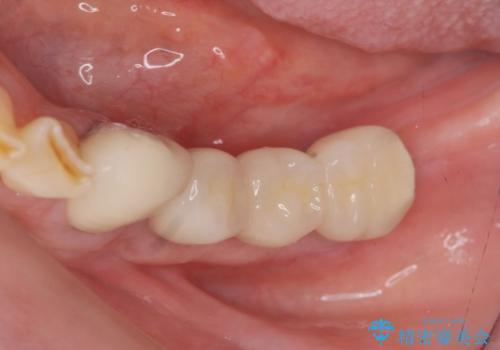

インプラントを埋入することで入れ歯のように取り外しをする必要がなくしっかりと噛めるような状態になり、大変治療結果に満足していただくことができました。